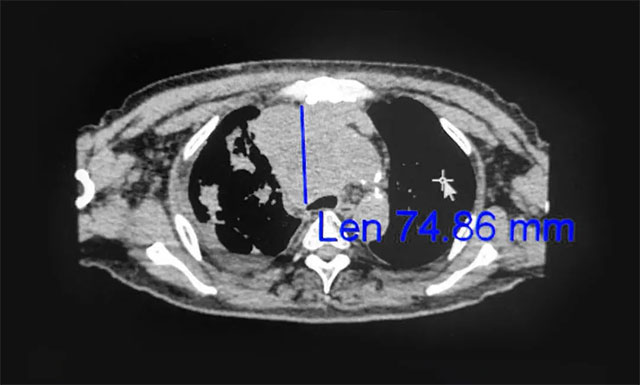

▲ 放疗后